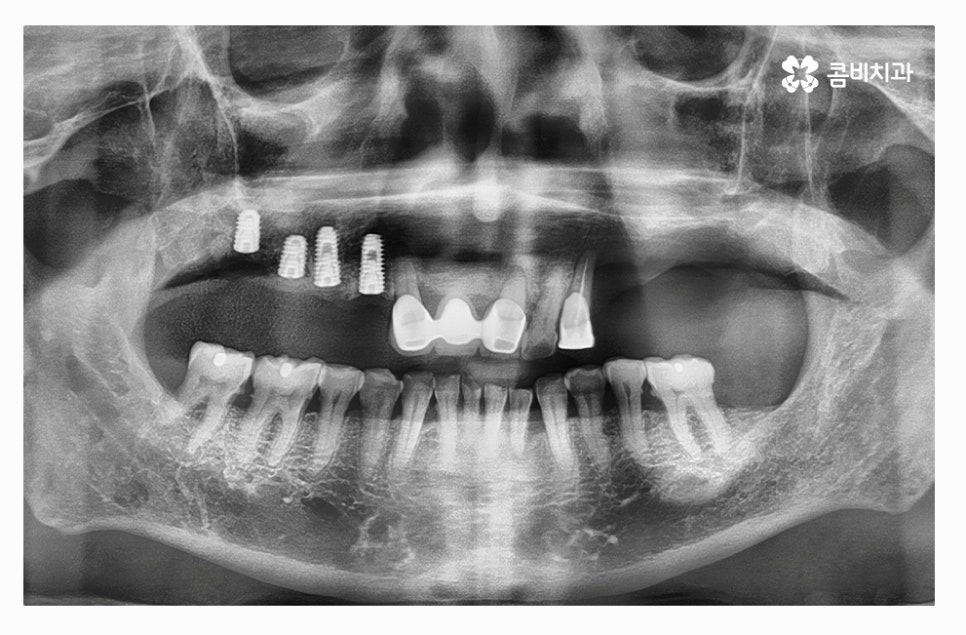

전체임플란트를 해야 할 때 주의사항은 잇몸을 최대한 보존하고

임플란트를 한꺼번에 식립해야 하기 때문에 3D CT 등을 활용한

정밀검진부터 철저하게 해야 하고 식립 각도 하나하나에

철저해야 하기 때문에 의료진의 경험과 실력이 중요한 시술이라 할 수 있어요.

만성치주염 환자분들의 경우 치아를 한꺼번에 발치한 후에

전체임플란트 치료 과정을 거치는 것 자체가

고난도의 시술이며 비용도 만만치 않지만

치료를 안전하게 마무리하고 수명을 오랫동안

건강하게 유지하는 것이 무엇보다 중요하다고 할 수 있는데요